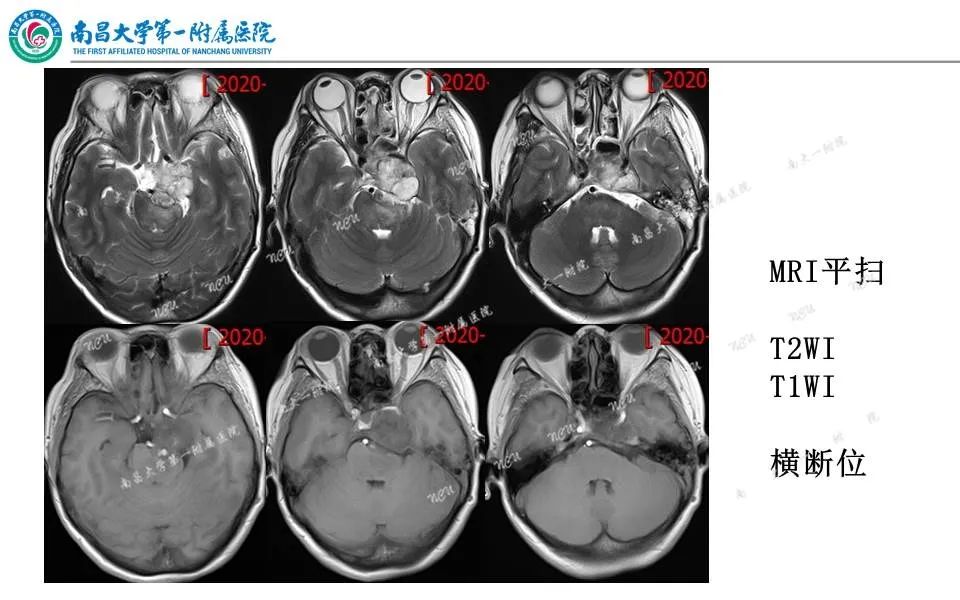

【PPT】颅底肿瘤的影像诊断思路